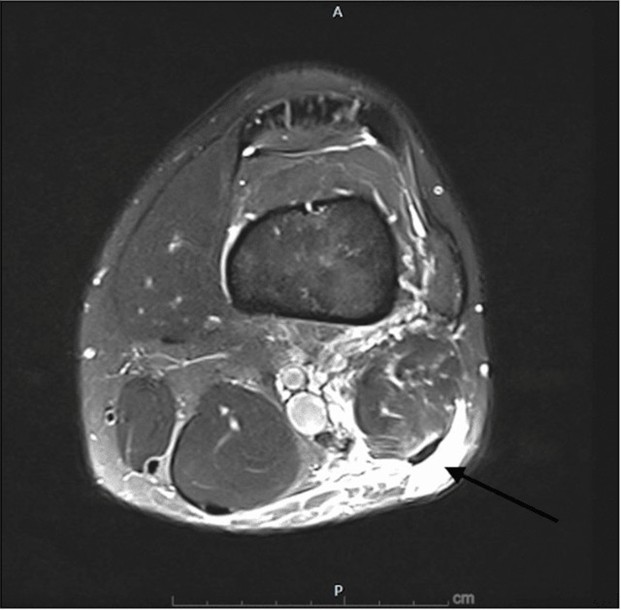

Given the clinical findings, an MRI of the left knee was obtained the same day, shown in Figures 1-3. Imaging revealed a near-complete tear of the distal biceps femoris tendon at the musculotendinous junction, approximately 5 cm proximal to its fibular insertion. Importantly, the tendon remained in continuity with the fibular head, with no frank avulsion. The lateral collateral ligament and posterolateral corner structures appeared intact [7].

Figure 3. MRI (axial view) of initial injury. Edema within the distal biceps femoris.